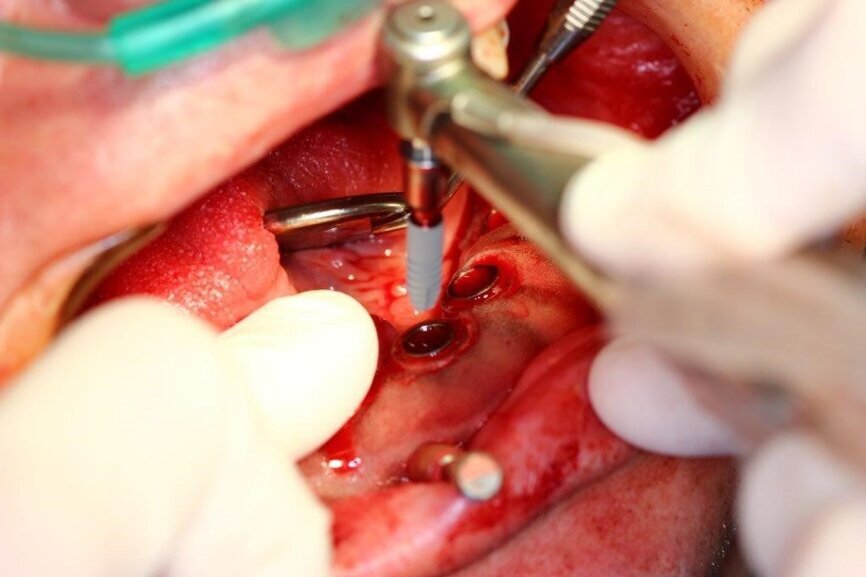

Zabieg wykonano w znieczuleniu ogólnym. Pobrano 72 ml krwi w celu uzyskania osocza bogatopłytkowego. Usunięto zęby paradontalne w żuchwie, a następnie umocowano szablon do kości żuchwy w 3 punktach: w linii pośrodkowej wyrostka oraz w okolicy 45 i 35, za pomocą wąskich pinów. Po sprawdzeniu prawidłowości osadzenia szablonu i nacięciu punchem śluzówki w wyznaczonych miejscach przez tuleje, zdjęto szablon w celu usunięcia wyciętej śluzówki.

Następnie przytwierdzono ponownie szynę i kolejnymi wiertłami zaopatrzonymi w stopery rozpoczęto preparację łoża dla implantów. Podczas pracy pozyskiwano kość własną pacjenta w celu późniejszej augmentacji. Po przygotowaniu wszystkich miejsc implantacyjnych przystąpiono do wprowadzenia wszystkich 8 implantów poprzez tuleje w szablonie, a następnie usunięto szablon z jamy ustnej pacjenta i założono śruby gojące. Kolejnym etapem pracy było wprowadzenie 5 implantów tymczasowych oraz zaopatrzenie zębodołów poekstrakcyjnych materiałem kostnym własnym pacjenta zmieszanym z materiałem ksenogennym i osoczem. Augmentat pokryto błonami PRF i zaszyto śluzówkę. Wprowadzono antybiotykoterapię. Wykonano zdjęcie CBCT kontrolne po zabiegu.